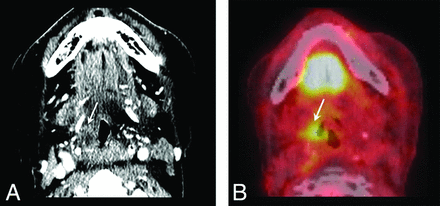

Finally, NI-RADS 3 is reserved for a discrete, nodular, robustly enhancing lesion (Fig 7A) with marked FDG uptake if PET was also performed (Fig 7B), and the recommendation is for biopsy. In the neck, NI-RADS 3 is a new or enlarging lymph node (Fig 8A) with marked FDG uptake if PET is combined (Fig 8B). The positive predictive value for NI-RADS 3 primary site lesions was lower (54.6%) than for the neck (70%); this finding likely reflects the more complex posttreatment imaging appearance at the primary site. Overall, we believe that the NI-RADS template yielded a reasonable rate of recommending biopsy. Only 32 of 618 possible targets (5.2%) were scored category 3 with biopsy recommendation, balanced against a relatively high positive predictive value (54.6% for the primary site, 70% for the neck).

NI-RADS neck category 3: new or enlarged lymph node. T2N0 oral cavity squamous cell carcinoma status post resection, neck dissection, and adjuvant radiation therapy. A, CECT at 6-month intervals shows enlarging left level 1B lymph node with necrosis (arrows). B, Fused PET images show marked focal FDG uptake (arrow). Revision neck dissection was positive for disease recurrence.